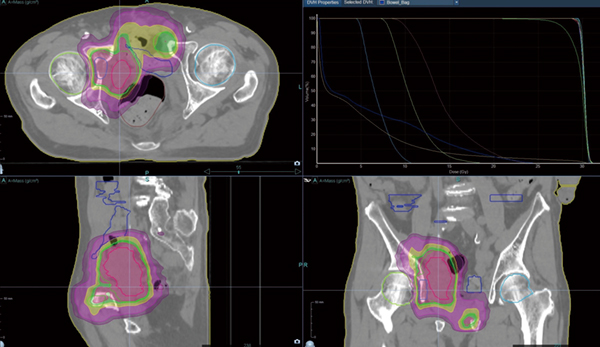

ヘリカル回転およびダイレクト照射による緩和照射への応用もRadixactは非常に有効である。図2のように,骨盤内播種,多発性骨転移の症例では,複数の有症状部位に対して同時に照射可能であり,患者の負担も軽減できる。また,進行食道がんや原発性肺がんに対する根治的な化学療法併用の通常分割照射にも十分に対応可能である。

図2 多発性転移(膀胱がん術後骨盤内播種,恥骨・右臼蓋骨転移)に対する緩和照射

Beam on time 247秒